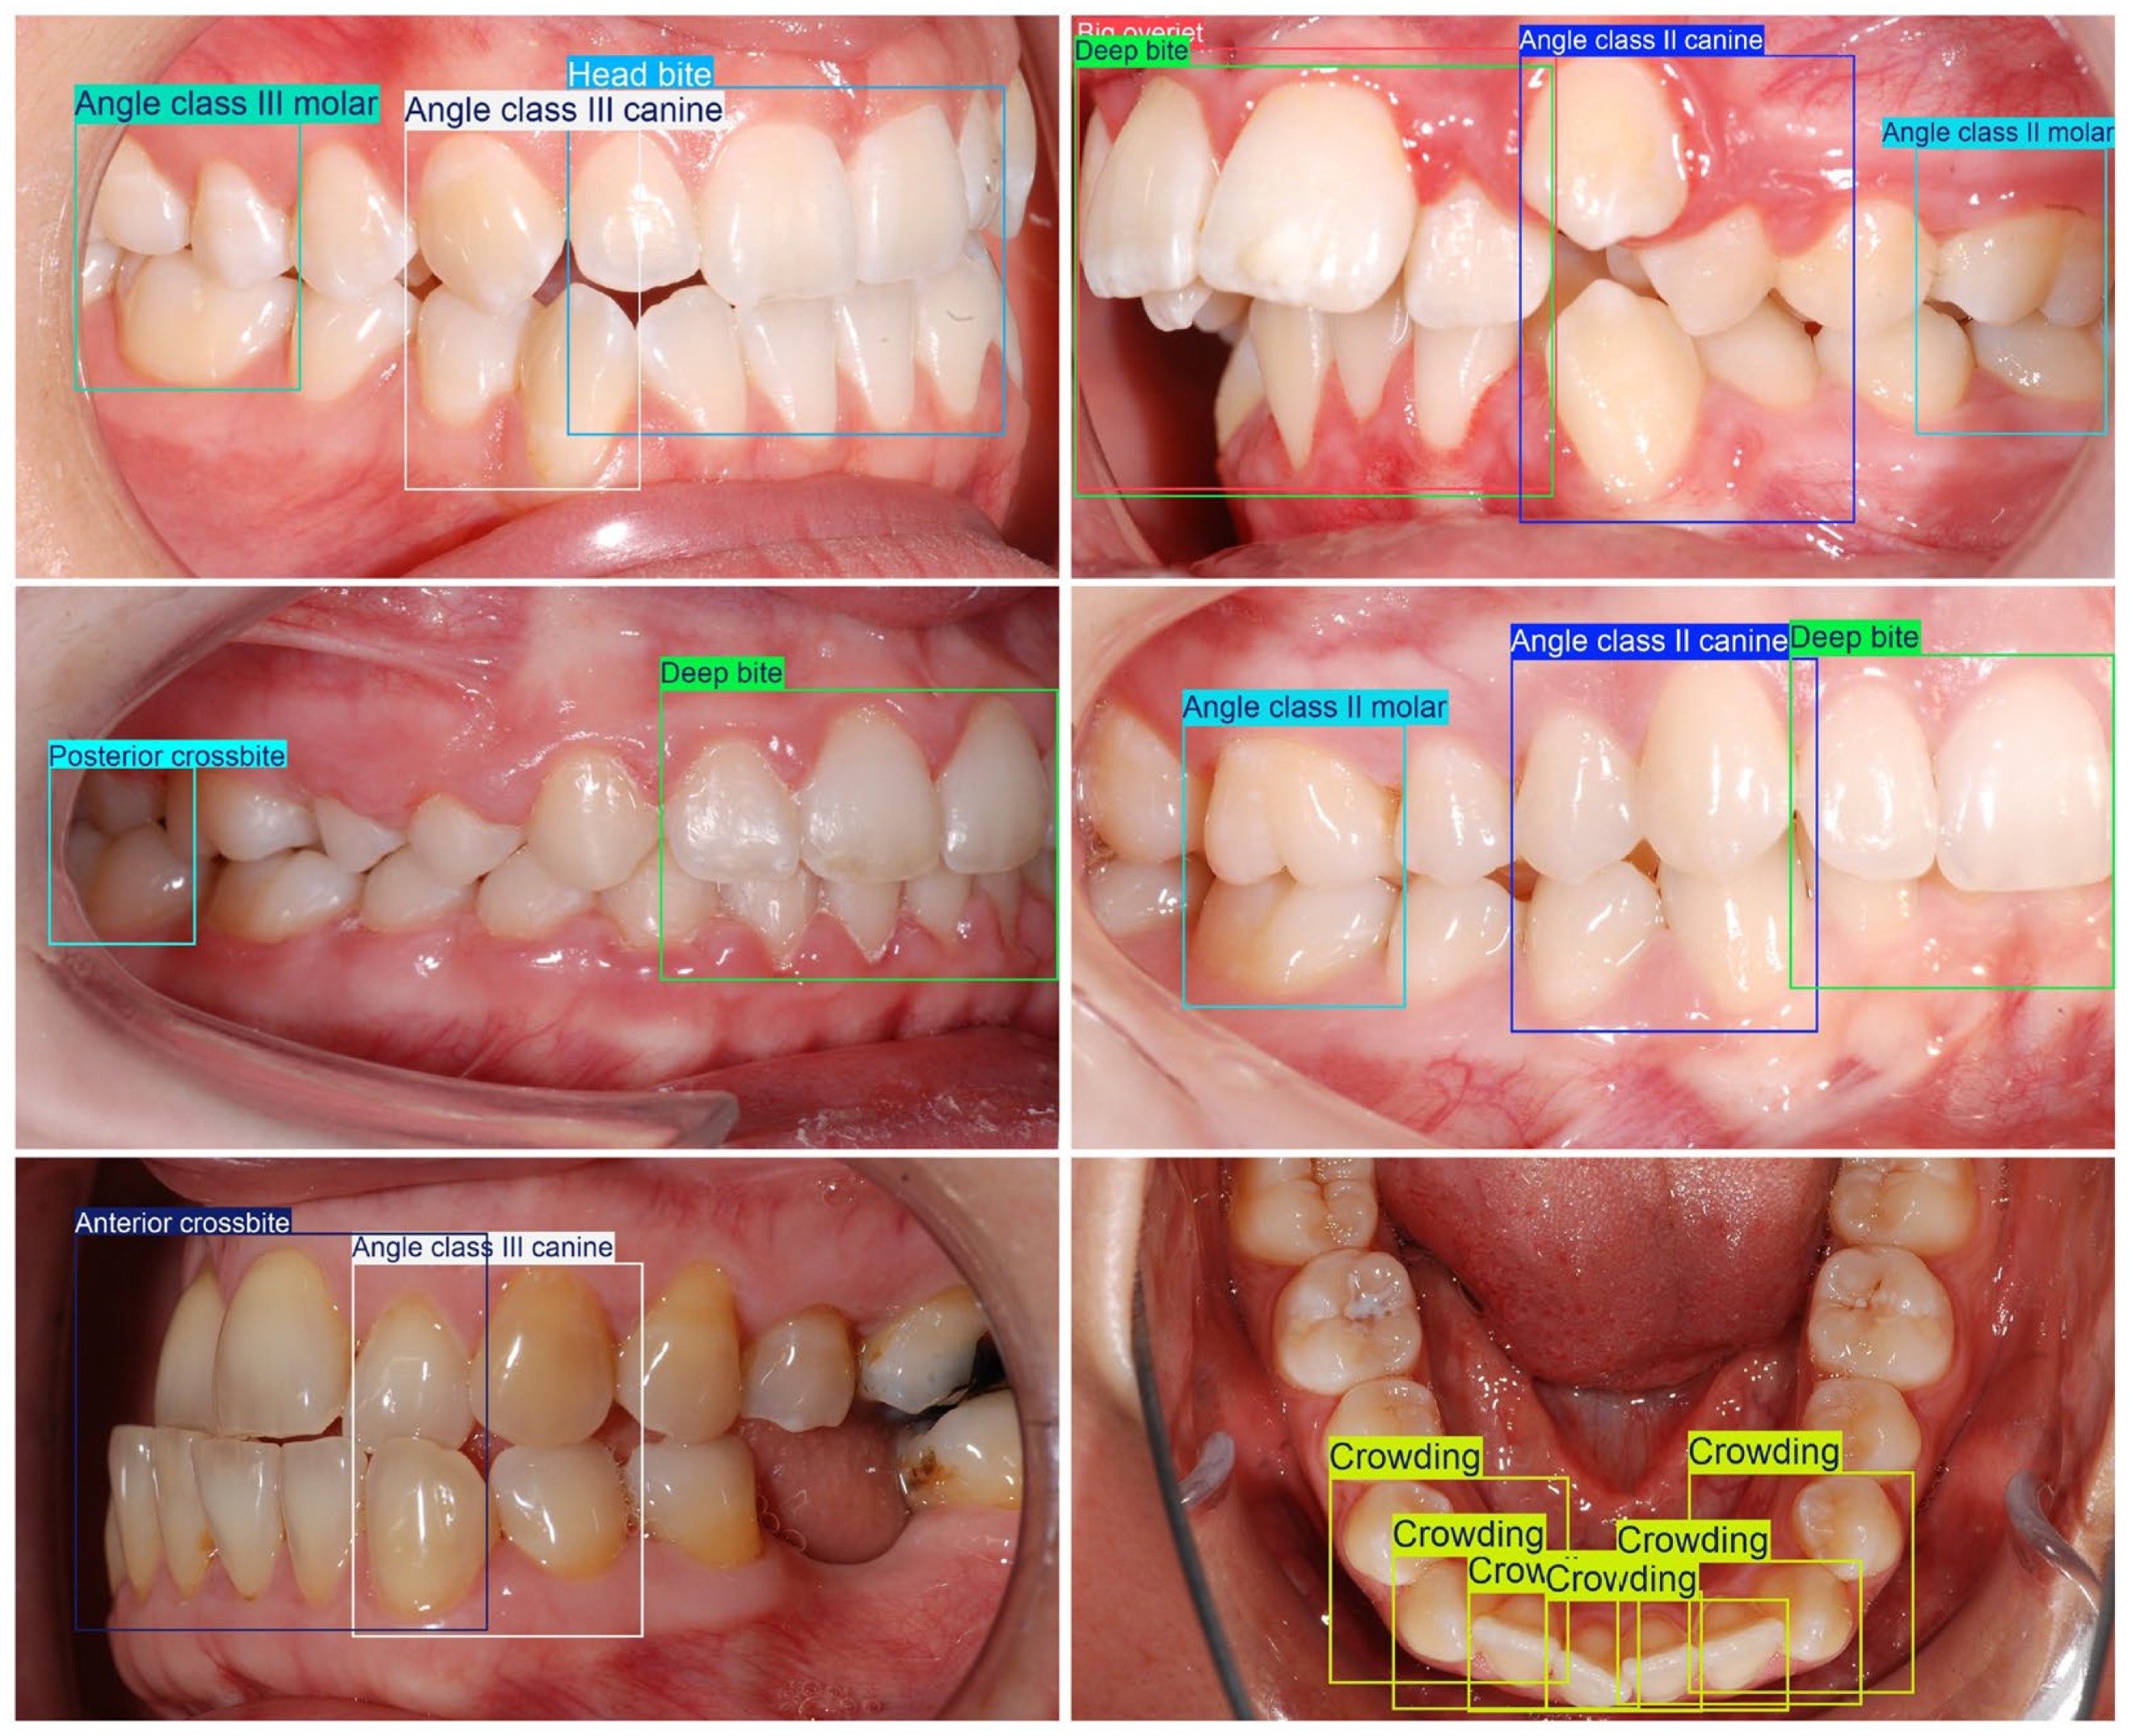

| Angle Class II molar, Angle Class III molar | BB over the first maxillary and mandibular molar |

| Angle Class II canine, Angle Class III canine | BB over the affected upper and lower canines, as well as the first lower premolar |

| Crowding | BB over the affected tooth as well as the two adjacent teeth |

| Angle Class II canine | The maxillary canine cusp tip is positioned mesial/anterior to the ideal embrasure between the mandibular canine and 1st premolar |

| Angle Class II molar | The mesiobuccal cusp of the maxillary 1st molar is anterior/mesial to the buccal groove of the mandibular 1st molar |

| Angle Class III canine | The maxillary canine cusp tip is positioned distal to the ideal embrasure between the mandibular canine and 1st premolar |

| Angle Class III molar | The mesiobuccal cusp of the maxillary 1st molar is posterior/distal to the buccal groove of the mandibular 1st molar |

| Crowding | Insufficient space in the arch, causing overlapping, rotations, or displacement of teeth |

| Deep bite | Mandibular incisors are covered too much by maxillary incisors (>50% coverage) |

| Head bite | Incisal edge-to-edge relationship: upper and lower incisors meet edge-to-edge with ~0 overjet |